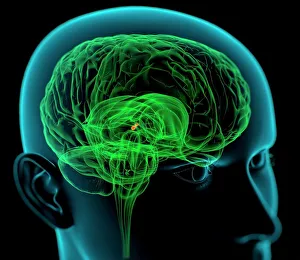

The central nervous system, the intricate network that governs our every thought and movement, is a marvel of complexity. From the delicate cerebellum tissue to the detailed light micrograph capturing its essence, we are reminded of its importance in maintaining balance and coordination. Anatomy comes alive as we explore the human brain from an inferior view. The intricacy of brain fibers is revealed through DTI MRI scans like C017/7099 and C017/7035, showcasing their vital role in transmitting information throughout this extraordinary organ. Artistic renderings bring us closer to understanding the medulla oblongata's significance within the brain. Its portrayal in various artworks allows us to appreciate how it controls essential functions such as breathing and heart rate. As we delve deeper into studying the central nervous system, models of the human brain provide invaluable insights into its structure and organization. Lateral views reveal countless regions responsible for cognition, emotion regulation, sensory perception, and motor control. Microscope slides offer glimpses into nerve cells' intricate architecture—a testament to their ability to transmit electrical signals at lightning speed. Meanwhile, glial stem cell cultures captured under a light microscope remind us of their crucial role in supporting neuronal function. Finally, artistic representations unveil the limbic system's enigmatic nature—an interconnected web responsible for emotions and memory formation. These captivating artworks allow us to visualize this complex network within our brains. Exploring these hints provides a glimpse into the awe-inspiring world of our central nervous system—the very foundation upon which our thoughts, actions, memories reside—reminding us just how remarkable our brains truly are.